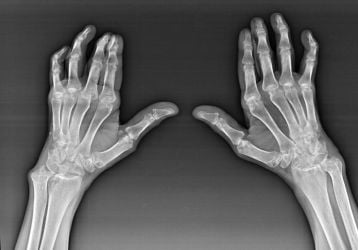

Артроз лучезапястного сустава: причины, симптомы, лечение

Артрорз лучезапястного сустава: стадии, способы диагностики методы лечения при помощи НПВП и хондропротекторов. Гимнастика для кистей.